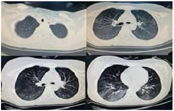

辅助检查:(1)脑脊液检查:生化指标、蛋白均在正常范围内。血清甲状腺功能、肌酶均阴性。(2)痰培养:铜绿假单胞杆菌。G实验、GM实验均阴性。(3)胸部CT:双肺炎症,双肺背侧肺野部分不张并实变(图1)。(4)膈肌功能超声:呼吸末膈肌厚度约1.1 mm,吸气末膈肌厚度约1.4 mm,膈肌增厚度约27%,膈肌移动度10 mm(图2)。(5)支气管镜:右肺中下叶、左肺下叶各级支气管可见大量痰液(图3)。

经后续20 d康复治疗:患者言语清晰,胸部CT双肺炎症明显吸收(图6),膈肌功能较前改善(图7)。拔出气切管。目前患者上、下肢关键肌肌力均达Ⅴ级。坐位平衡3级,可独立步行。ADL BI评分85分(进食10分、修饰5分、穿衣10分、控制大便10分、控制小便10分、如厕10分、床椅转移15分、平地行走15分)。